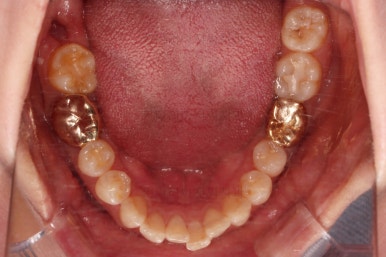

아랫니 부분교정이 끝났고요.

어금니도 원위치로 많이 갔네요.

아랫니 부분교정과 어금니 부분교정은 비교적 조기에 끝났으나(7개월) 임플란트가 생각보다 오래 걸렸습니다.

치료 종료시의 모습인데요.

임플란트가 잘 들어갔고 아래 앞니도 원하는 모습으로 잘 배열이 되었습니다.